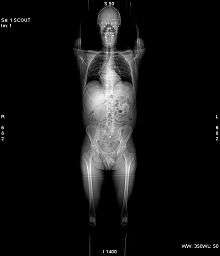

A CT scan makes use of computer-processed combinations of many X-ray images taken from different angles to produce cross-sectional (tomographic) images (virtual "slices") of specific areas of a scanned object, allowing the user to see inside the object without cutting.

Digital geometry processing is used to generate a three-dimensional image of the inside of the object from a large series of two-dimensional radiographic images taken around a single axis of rotation.[2] Medical imaging is the most common application of X-ray CT. Its cross-sectional images are used for diagnostic and therapeutic purposes in various medical disciplines.[3] The rest of this article discusses medical-imaging X-ray CT; industrial applications of X-ray CT are discussed at industrial computed tomography scanning.

CT produces a volume of data that can be manipulated in order to demonstrate various bodily structures based on their ability to block the X-ray beam. Although, historically, the images generated were in the axial or transverse plane, perpendicular to the long axis of the body, modern scanners allow this volume of data to be reformatted in various planes or even as volumetric (3D) representations of structures. Although most common in medicine, CT is also used in other fields, such as nondestructive materials testing. Another example is archaeological uses such as imaging the contents of sarcophagi. Individuals responsible for performing CT exams are called radiographers or radiologic technologists.[4][5]

Two-dimensional CT images are conventionally rendered so that the view is as though looking up at it from the patient's feet.[57] Hence, the left side of the image is to the patient's right and vice versa, while anterior in the image also is the patient's anterior and vice versa. This left-right interchange corresponds to the view that physicians generally have in reality when positioned in front of patients.